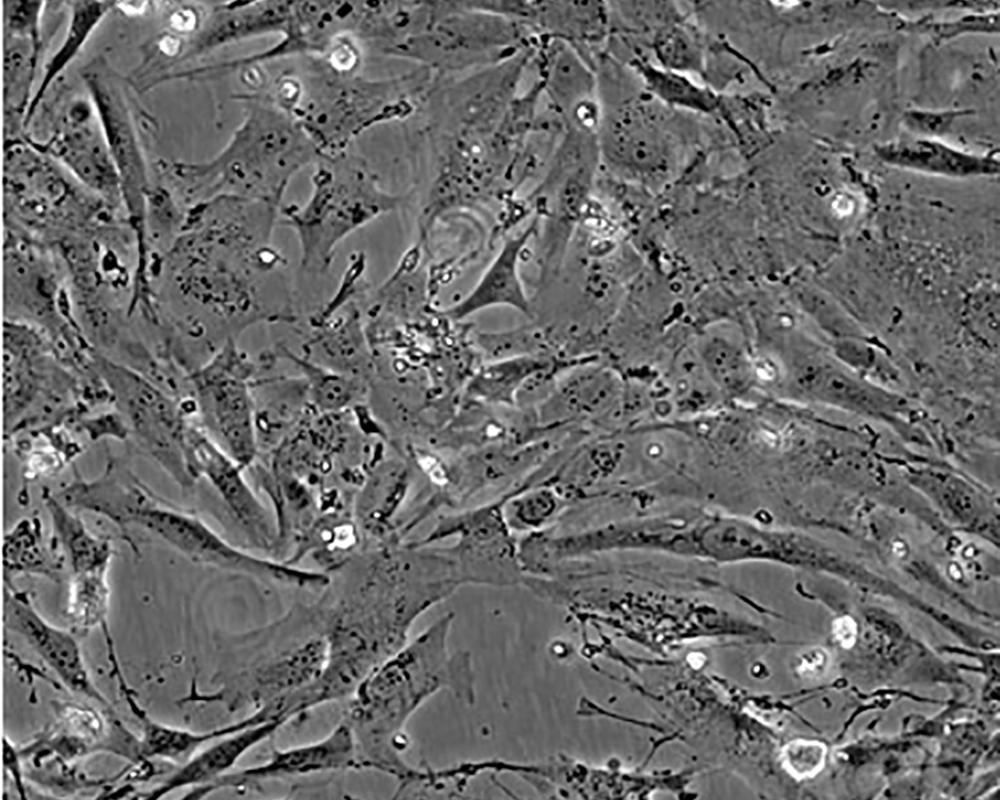

細(xì)胞描述 The Hs 578T line had a mixed polygonal morphology initially, but a stellate cell type was selected for during passage and by cloning. Aggregates of casein protein granules, desmosomes, tight junctions, lipid droplets and vesicularized smooth endoplasmic reticulum were observed by electron microscopy. As with Hs 578Bst, no estrogen receptors or endogenous viruses were detected.